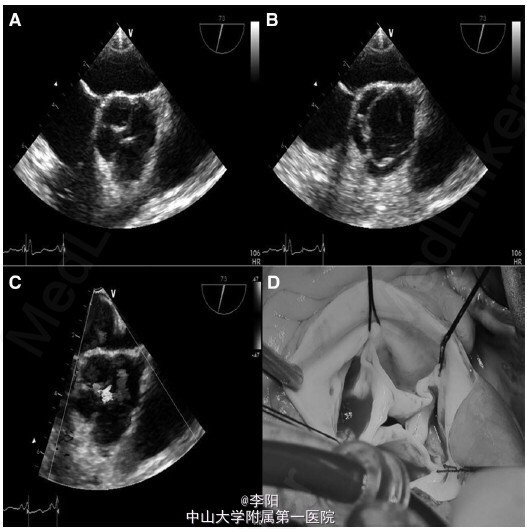

患者,女,35 岁,因车祸入院,既往曾行直肠阴道瘘修补术,诉劳力性呼吸困难多年。面部特征表现为双侧耳前凹陷、脸部不对称。查体提示左侧第二肋间舒张期杂音。血常规、心电图、胸片均未见异常。超声心动图提示升主动脉扩张(39mm),主动脉瓣重度反流。经食管超声心动图提示四叶式主动脉瓣(图 1A-1C)。增强 CT 显示双下腔静脉系统、半奇静脉及持续性上腔静脉异常,冠状动脉窦动脉瘤并主动脉四叶瓣 (图 2A-2D)。